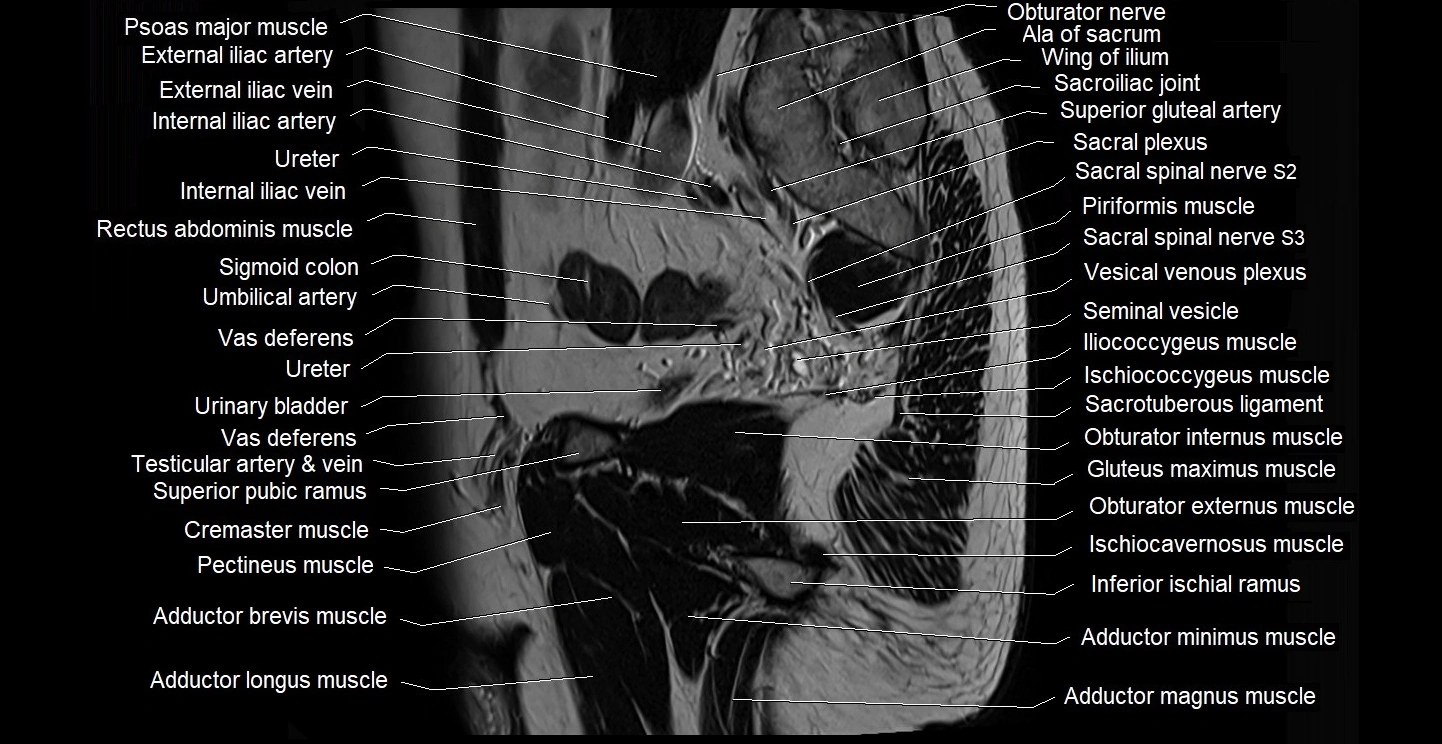

- Adductor brevis muscle

- Adductor longus muscle

- Adductor magnus muscle

- Adductor minimus muscle

- External iliac artery

- External iliac vein

- Internal iliac artery

- Internal iliac vein

- Obturator internus muscle

- Obturator nerve

- Pectineus muscle

- Piriformis muscle

- Sacral plexus

- Sacroiliac joint

- Sciatic nerve

- Seminal vesicle

- Sigmoid colon

- Superior gluteal artery

- Urinary bladder

- Vas deferens